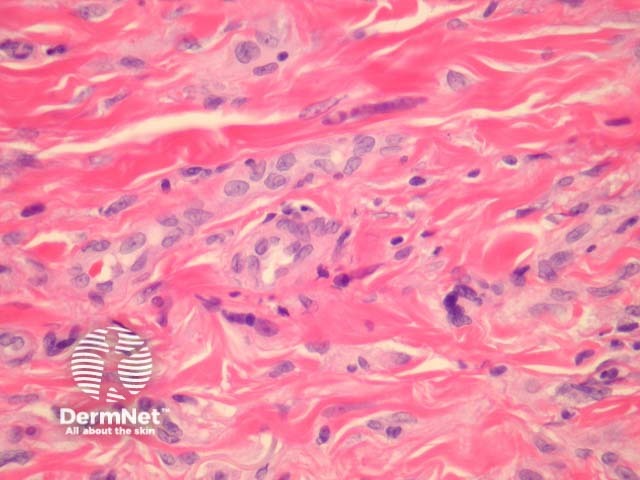

In multinucleate cell angiohistiocytoma, sections show abundant small dilated blood vessels and fibroplasia, principally in the mid-dermis (figure 1, 2). Higher power shows scattered bizarre cells (figures 3, 4) showing a pale basophilic cytoplasm and several nuclei arranged at the cell periphery (figure 3, arrow). A perivascular inflammatory infiltrate may also be seen.

Figure 3

Figure 4